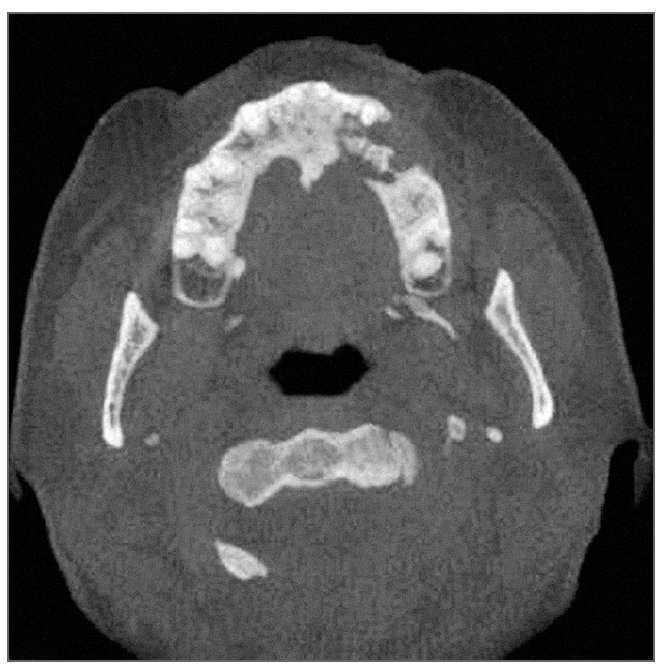

Las radiografías periapicales obtenidas antes de la extracción de los premolares (fig. 1) pusieron de manifiesto un ensanchamiento del ligamento periodontal en el primer premolar superior izquierdo que se extendía desde la cresta del reborde alveolar hasta la región apical tanto en mesial como en distal, con signos de osteítis y rarefacción apical. También se observaba ensanchamiento del ligamento periodontal en el segundo premolar superior izquierdo. Las áreas apicales de ambos dientes presentaban una esclerosis creciente que se extendía hasta el borde cortical del suelo del seno maxilar confundiéndose con él. Tras la extracción del primer premolar superior izquierdo se tomó una radiografía panorámica (fig. 2) en la que se observaba el alvéolo de extracción y signos de osteítis y rarefacción apical alrededor de la raíz del segundo premolar que se extendían hasta la cresta del reborde alveolar. El segundo premolar superior izquierdo se extrajo poco después.

Figura 1. Radiografía periapical del primer premolar superior izquierdo que muestra la región apical de ambos premolares en el momento de la presentación inicial.